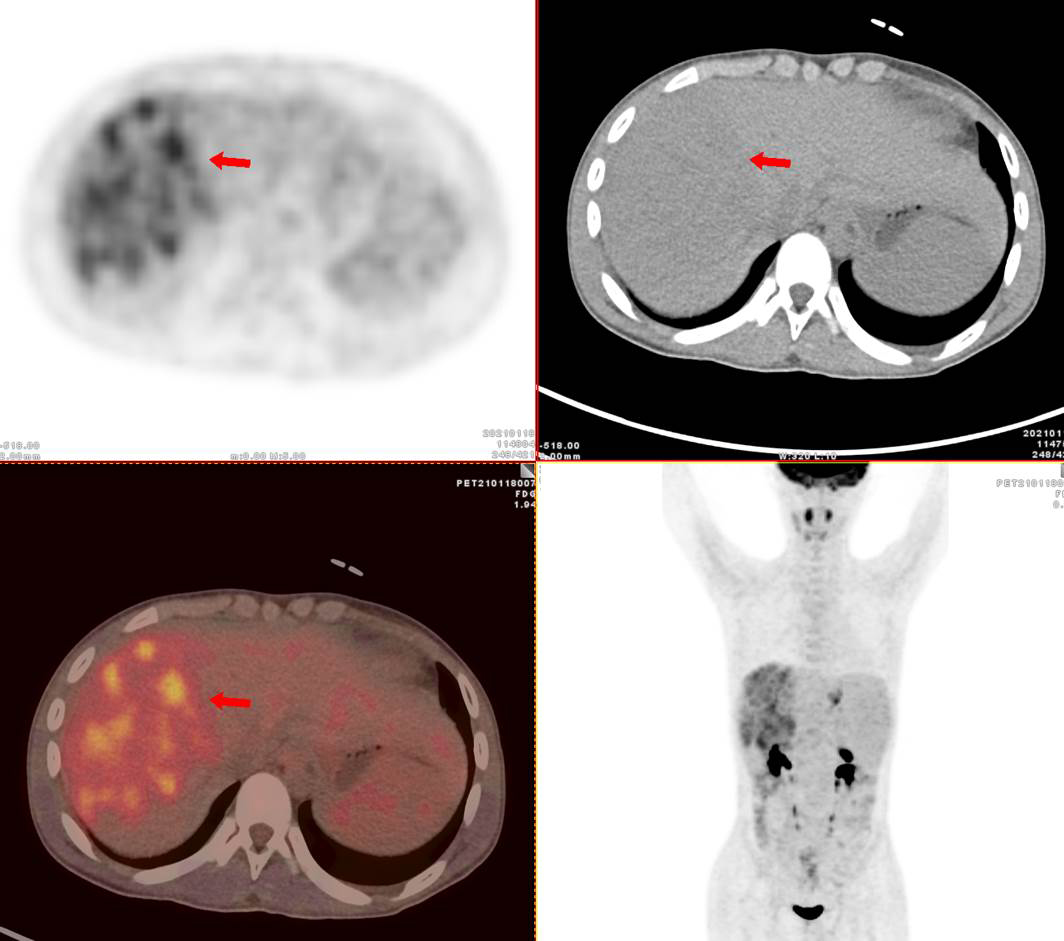

69歲王老伯,發(fā)現(xiàn)肝占位2月余,口服靶向藥物治療,近期外院CT發(fā)現(xiàn)肝多發(fā)占位,診斷為肝細胞肝癌并肝內(nèi)轉(zhuǎn)移,查血腫瘤標記物,AFP 5410ng/ml,有乙肝病史。

PET/CT顯示肝臟左右葉內(nèi)多發(fā)大小不等稍低密度結(jié)節(jié),最大病灶5.8x5.5cm,密度不均,F(xiàn)DG攝取不同程度最高,SUVmax3.9-9.6,門靜脈右支增寬,F(xiàn)DG攝取最高,SUVma 4.9。

PET/CT診斷:原發(fā)性肝細胞肝癌 (多發(fā)結(jié)節(jié)型)并壞死、出血、門靜脈右支癌栓形成;肝硬化